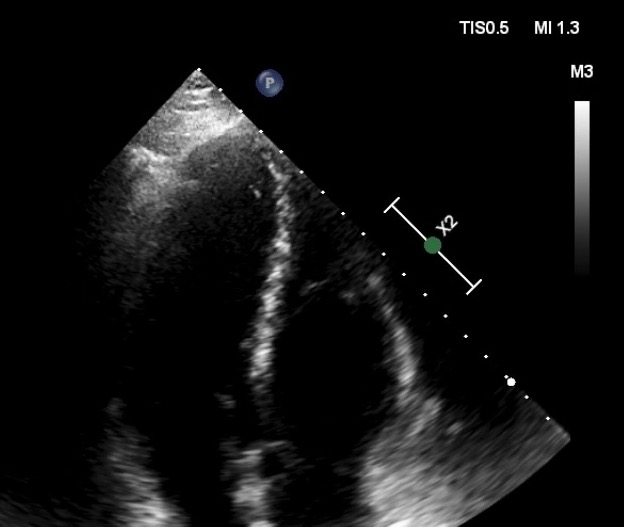

45 yaşlı kişi xəstə sağ ayaqda anidən yaranmış şişkinlik, kəskin ağrı, təngnəfəslik şikayəti ilə xəstəxanamızın təcili tibbi yardım şöbəsinə müraciət etmişdir. Xəstə 10 il əvvəl mielit keçirmiş və sağ aşağı ətrafın hissəvi parezi mövcuddur. Passiv həyat tərzi keçirdiyini, günün çox hissəsini evdə hərəkətsiz vəziyyətdə olduğunu qeyd edir. Xəstəyə dərhal exokardioqrafiya olundu və sağ boşluqların genişləndiyi, ağciyər arteriyasının sistolik təzyiqinin artmış (50mmHg) olduğu görüldü. Daha ətraflı müayinə zamanı sol və sağ qulaqcıq daxilində də hərəkətli kütlənin olduğu görüldü. Xəstəyə transezofageal exokardioqrafiya tövsiyə edildi, lakin xəstə bu müayinədən imtina etdi. Aşağı ətraf venalarının doppler müayinəsi zamanı sağ dizaltı venanın kəskin trombozu aşkarlandı. Sol və sağ qulaqcıq daxilindəki hərəkətli kütlənin tromb (Şəkil 1,2 və 3) ola biləcəyi düşünüldü və xəstə hospitalizasiya edildi. Xəstəyə gündəlik 30 mq (15 mq x 2 dəfə) rivaroksaban başlanıldı. Sağ aşağı ətraf üçün kompression corab təyin edildi. Müalicənin beşinci günü təkrari exokardioqrafiya olundu (Şəkil 4 və 5). Bu zaman görülən hərəkətli kütlələr görülmədi, sağ mədəciyin ölçüləri normallaşmış, ağciyər arteriyasının sistolik təzyiqi isə 35mmHg-na qədər enmişdir. 21 gün sonra rivaroksabanın dozası gündəlik 20 mq təyin edildi. Sağ aşağı ətrafda hissəsi parez olması səbəbindən rivaroksaban müalicəsi qeyri-müəyyən zamana qədər davam etdiriləcək.